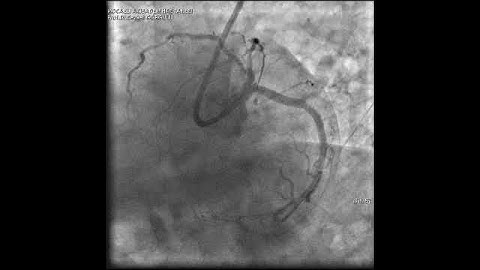

Tips & Tricks to wire a complex side branch ostial lesion!